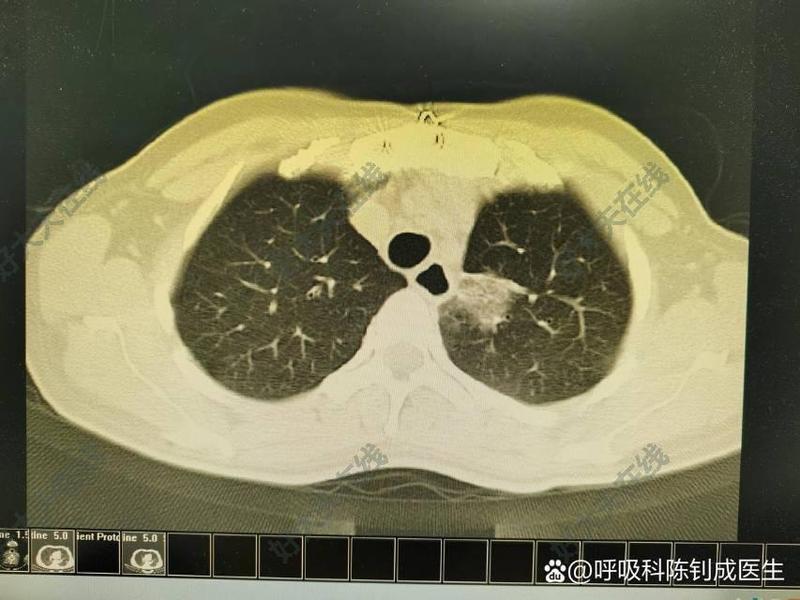

治療前患者45歲女性,因干咳氣促半月入院?;颊邿o咳痰,感染指標(biāo)不高,血?dú)夥治鍪镜脱跹Y。??治療中規(guī)范抗感染治療無效。纖支鏡檢查鏡下未見異常。肺泡灌洗液以淋巴細(xì)胞為主。中間復(fù)查胸部CT肺部滲出病灶有游走性表現(xiàn)。追問病史發(fā)病前有接觸染發(fā)劑史??紤]過敏性肺炎,予激素治療后肺部滲出吸收。治療后治療后1月自行停藥后復(fù)發(fā),再次激素治療后吸收好轉(zhuǎn)。